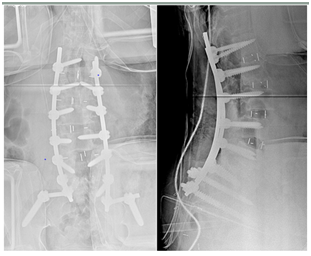

Selective segmental osteotomies

- Mostly Trans pedicular resection osteotomies

- Vertebral De- cancellation osteotomy

- Wedging osteotomy for the associated kyphosis.

- Total Vertebrectomy in one stage or two stages

- Vertebral column resection for the associated kyphosis in particular, but not used with degenerative scoliosis so frequently.

- These techniques became more frequently required for balance restoration in rigid and severely rigid curves of the thoracic and lumbar spine.1 (Figure 4a & 4b).

Figure 4a Smith Petersen Osteotomy.

Figure 4b Three Column Pedicle Subtraction Osteotomy.

Smith Petersen Osteotomy |

Three Column Pedicle Subtraction Osteotomy |

For the patient requiring 10° to 20° of lordosis or 4 to 7 cm of correction of the C7 plum line. |

For the patient requiring 20° to 35° of lordosis or 10 cm of correction of the C7 plum line. |

Needs a mobile disc. |

_ |

The osteotomy hinges on the posterior aspect of the disk |

The osteotomy hinges on the anterior cortex |

Lengthens Ant Column. |

Shortens post Column. |